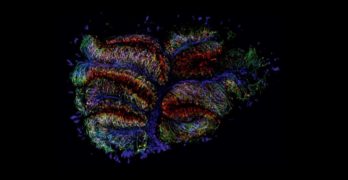

Ciencia, células y color: la apuesta artística del Hospital de Parapléjicos

El Círculo de Arte de Toledo acoge la exposición ‘Medularte’, una muestra organizada por la Unidad de Investigación del centro hospitalario para mostrar con fotografías la belleza de su trabajo